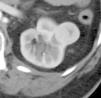

Objetivo. El oncocitoma es un tumor renal benigno, relativamente infrecuente. Hasta este momento su diferenciación radiológica del carcinoma de células renales se considera imposible, aunque hay escasos artículos en que se haya utilizado la tomografía computarizada (TC) trifásica. Los autores describen los hallazgos con TC trifásica en estos tumores, valorando si algunas características, aunque no diagnósticas, sí pudieran sugerir la posibilidad de este diagnóstico. Esto, en algunos casos, podría cambiar el manejo de los pacientes. Material y métodos. Se describen los hallazgos de TC trifásica en 10 casos de oncocitoma, vistos en 8 pacientes (un caso era multifocal-bilateral). En todos los casos el diagnóstico fue anatomopatológico, en la pieza de resección. Resultados. Todos los tumores fueron hallazgos ecográficos incidentales previos a la TC, presentando un tamaño muy variable, de 3 a 15 cm, con una media de 5,2 cm. El contorno era bien definido. Uno de los pacientes tenía tumores bilaterales (2 derechos y 1 izquierdo). Excepto en un tumor, el resto mostraban una cicatriz «estrellada» interna, que en un caso seguía un marcado patrón lobular. La captación tumoral de contraste fue ávida, con una media de 120 HU en fase arterial y 116 HU en fase excretora. La evolución de todos los pacientes fue buena, no detectándose recidivas postquirúrgicas. Conclusiones. Aunque la diferenciación con el carcinoma de células renales no puede hacerse con certeza, debe sugerirse la posibilidad de oncocitoma, fundamentalmente en tumores pequeños, con cicatriz central, ausencia de necrosis, falta de infiltración y un patrón de captación como el que se describe. Independientemente del tamaño, una morfología lobular del tumor también debe sugerir esta posibilidad.

Objective. Oncocytoma is a relatively uncommon benign kidney tumor. To date, it has been impossible to differentiate this tumor from renal cell carcinoma radiologically, although few articles report on the use of tri-phase CT in this tumor. We describe the triphasic CT findings in these tumors and evaluate whether some characteristics, although not sufficient to ensure the diagnosis, can suggest the possibility of oncocytoma. In some cases, this may lead to a different approach to the management of patients. Material and methods. We describe the tri-phase CT findings in 10 cases of oncocytoma in eight patients (one case was bilateral and multifocal). The diagnosis was made after histological examination of surgical specimens in all cases. Results. All the tumors were found incidentally at ultrasound examination prior to CT study. Tumors all had well-defined borders, and their size ranged from 3 to 15 cm, with a mean diameter of 5.2 cm. One patient had bilateral tumors (2 right and 1 left). All but one of the tumors had a star-shaped scar inside, with a marked lobular pattern in one case. All tumors showed avid uptake, with mean enhancement of 120 HU in the arterial phase and 116 HU in the venous phase. All patients evolved favorably with no post-surgical relapse. Conclusions. Although oncocytoma cannot be differentiated from renal cell carcinoma with certainty, the possibility of oncocytoma should be suggested in the case of small tumors with a central scar, without necrosis or infiltration, and an enhancement pattern as described here. Regardless of the size of the tumor, lobular morphology should also suggest this possibility.